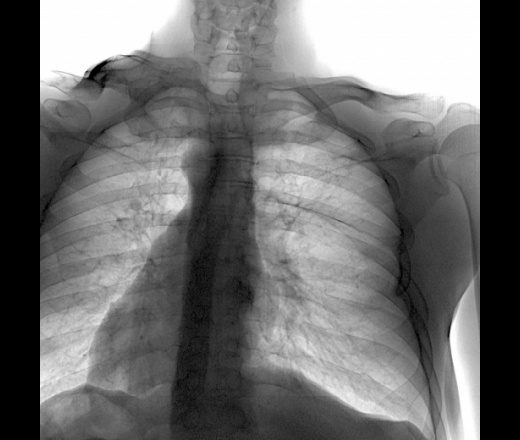

Рентгенофлюорографическое обследование — надежный способ раннего выявления туберкулеза и других скрыто протекающих болезней легких.

Флюорография позволяет диагностировать все случаи туберкулеза легких от малых до деструктивных форм и многообразную другую патологию органов грудной клетки: опухоли, воспаления легких.

Рентгенограмма легких взрослого мужчины с двусторонней пневмонией.PREMIUM